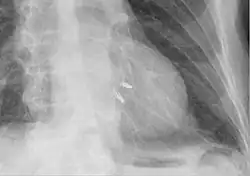

![]() Chest radiograph showing two MitraClips projecting over the heart. | |